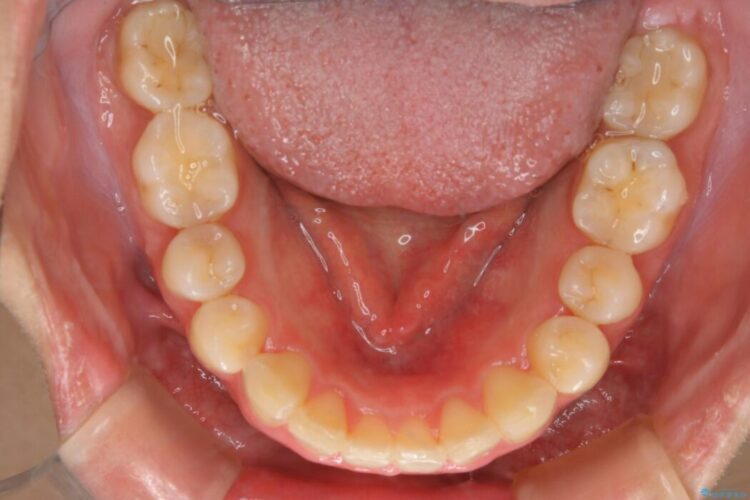

口ゴボに加えて歯列のガタガタを改善したいと来院されました。

患者様のご希望によりインビザライン装置での治療を行いました。

インビザラインは歯を後ろへ動かす動き、非抜歯での矯正治療が得意なため、ワイヤー装置では難しいケースでも対応できる場合があります。

矯正治療において歯並びを整えるためにはスペースが必要になります。

抜歯・歯列幅の拡大・IPR(歯と歯の間を少し削って小さくする)・歯の後方移動などでそのスペースを確保します。

程度にもよりますが口元を下げる治療というと抜歯治療を思い浮かべると思いますが、インビザラインは抜歯をせずとも他の3種類の方法を効率よく活用し治療ができます。